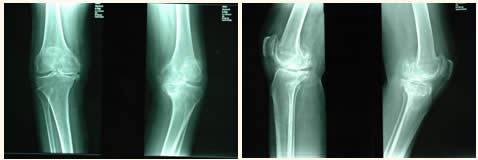

第一期:只有关节边缘骨质增生,关节间隙并不狭窄。

第二期:除有关节边缘骨质增生外,还有关节间隙变窄。

第三期:除有上述变化外,软骨硬化、还有软骨下囊性变。

第四期:关节已经毁坏,出现屈曲挛缩,X形腿或O形腿,并有不同程度的骨缺损。